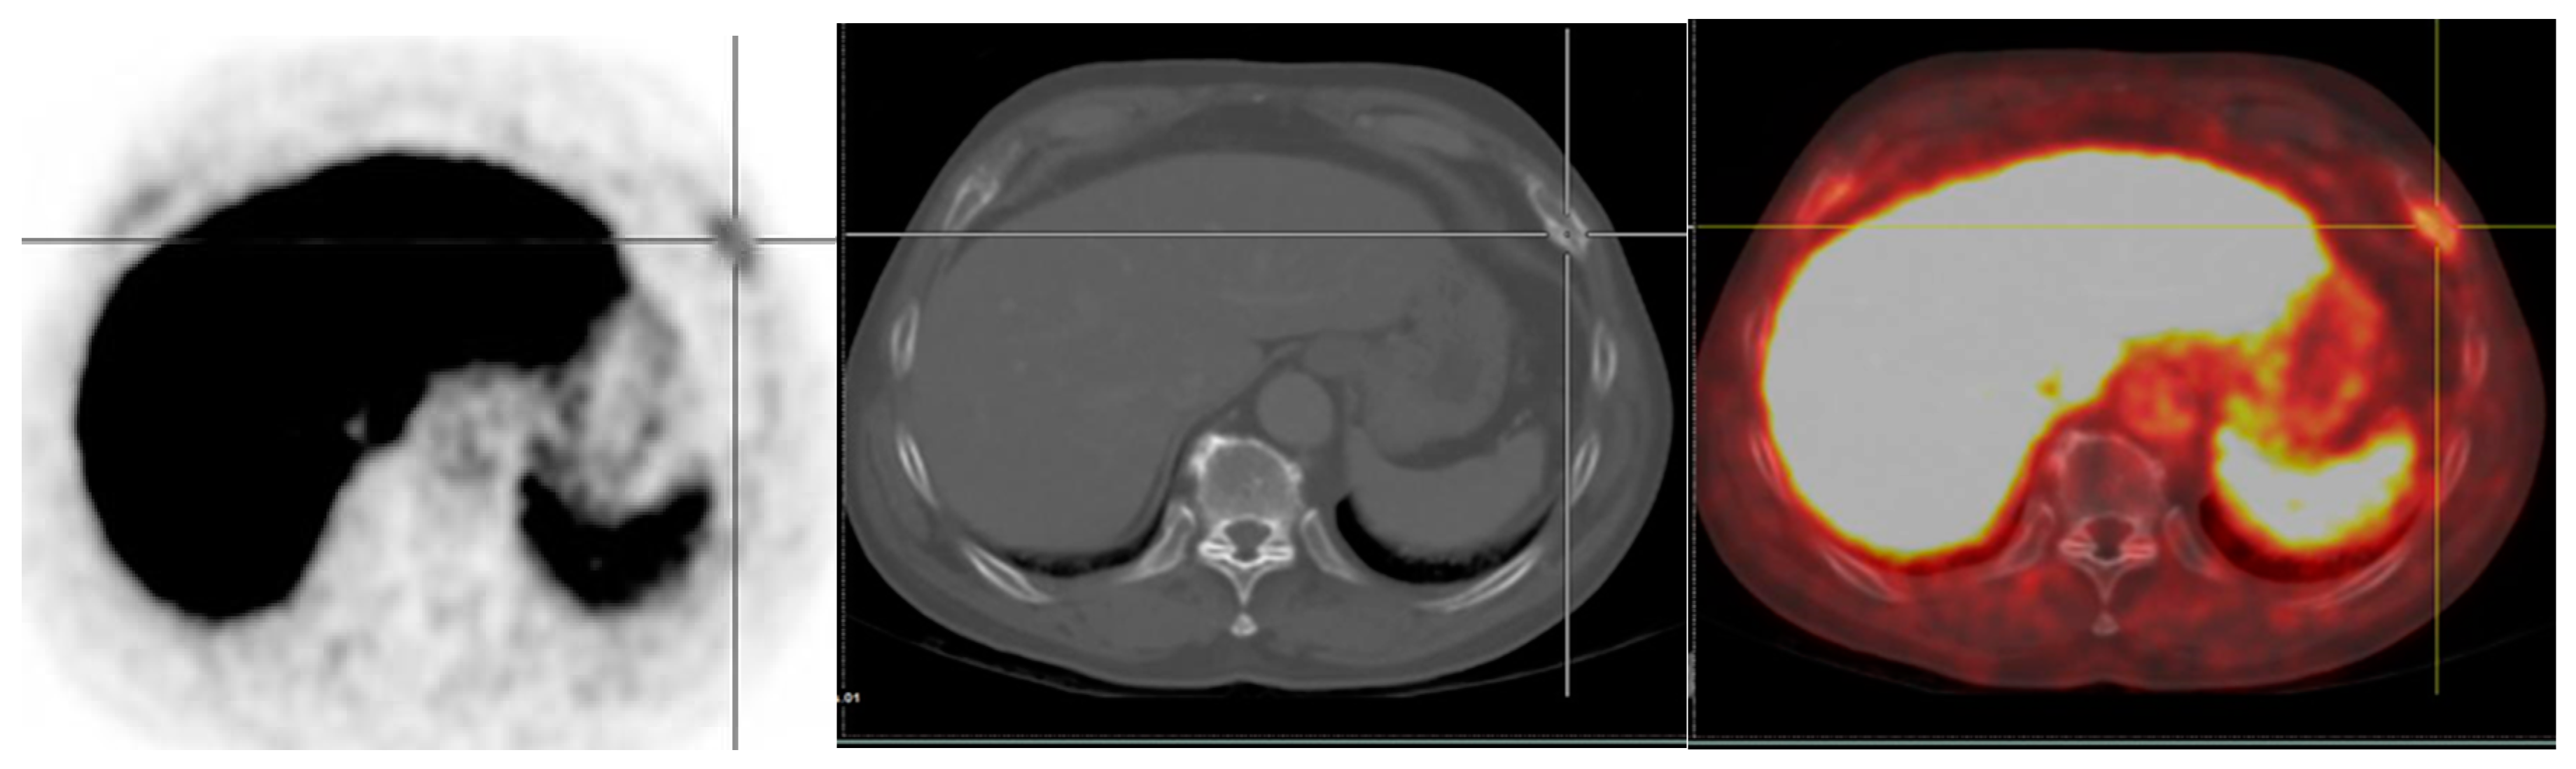

Figure 5.

A 75-year-old man with diagnosed PCa (Gleason score of 4 + 4, initial PSA of 43.12 ng/mL) who underwent 18F-PSMA PET/CT for initial staging. PET/CT scan reveals PSMA uptake at prostatic bed with multiple osteoblastic metastases at vertebrae. There are few subcentimeter mild PSMA-avid nodes at right lower paratracheal regions (SUVmax of 2.72) which are suspected of reactive nodes (A). Transaxial PET/CT in lung window (B) revealed increased PSMA uptake associated with reticulonodular infiltration at RUL which was suspected of pulmonary infection. After follow-up imaging, pulmonary lesion was improved, and mediastinal nodes revealed no significant change in size but no longer observable PSMA uptake.